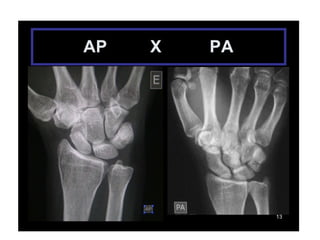

INCIDÊNCIAS PUNHO E MÃO